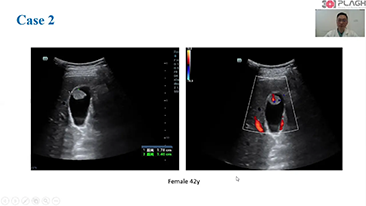

Los flujos de trabajo de OBG optimizados son necesarios para admitir grandes cantidades de pacientes para las visitas de evaluaciĂłn de la salud de las mujeres. Por ejemplo, las malformaciones del sistema nervioso central (SNC) son una de las anomalĂas congĂ©nitas mĂĄs comunes. Debido a las diversas condiciones del diagnĂłstico por imĂĄgenes, como una posiciĂłn fetal deficiente, el plano sagital medio (MSP) es particularmente difĂcil de obtener a partir de una ecografĂa 2D. Por lo tanto, la detecciĂłn y las mediciones automatizadas pueden mejorar en gran medida la eficiencia de la exploraciĂłn.